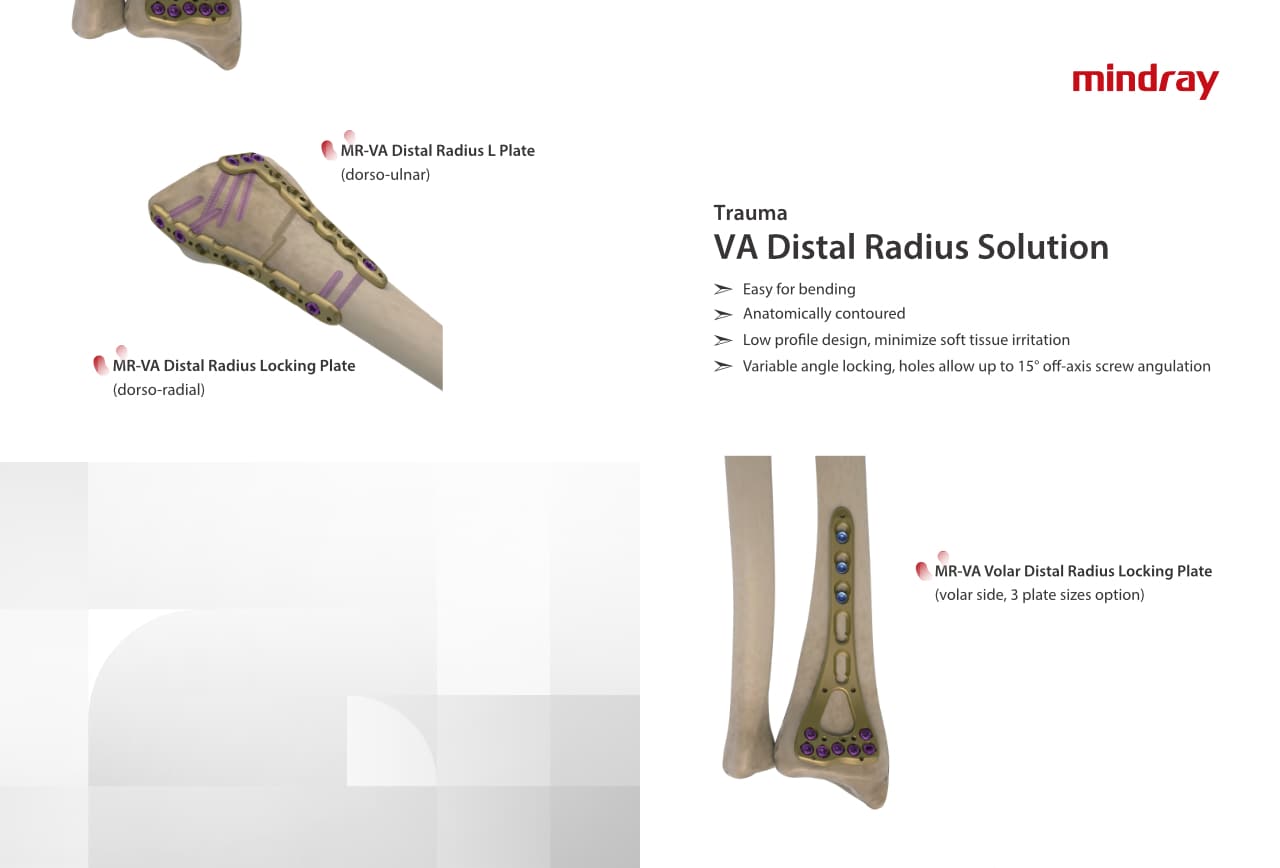

Traumatologie